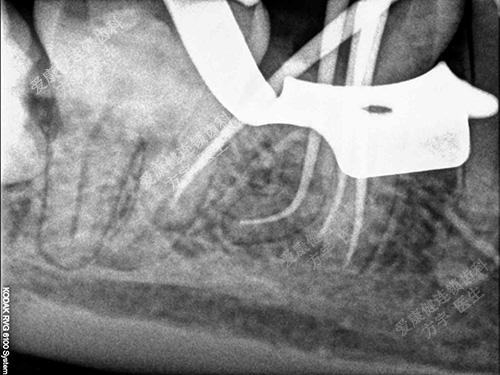

术前